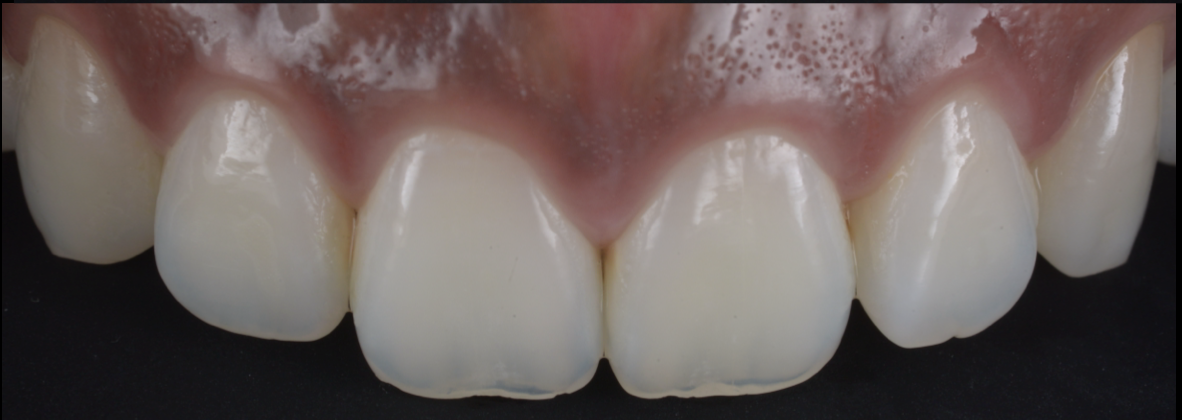

上唇の腫脹を認め、CT検査にて根尖部に嚢胞様透過像を認めた。左上の前歯が不自然に大きく噛み合わせが強くなっていたことがフレアアップの一因と考える。精密根管治療を行い、感染経路を遮断したのち歯根端切除術にて嚢胞を摘出した。

治療中

| 治療内容 | 精密根管治療、歯根端切除術、セラミック修復 |